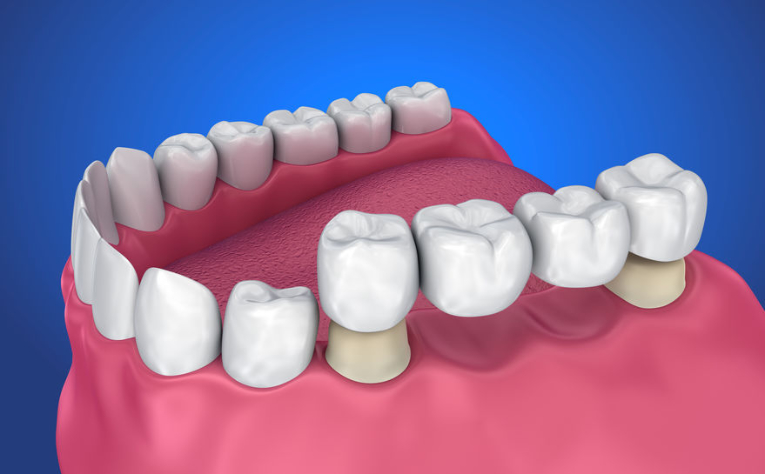

Most to konstrukcja używana w protetyce w celu uzupełnienia luki powstałej po brakującym zębie. Most protetyczny osadza się na bocznych zębach, które stanowią filary utrzymujące całą konstrukcję. W tym celu zęby stanowiące filar muszą zostać poddane częściowemu oszlifowaniu. Alternatywą dla mostu jest implant zębowy

Jak wygląda zakładanie mostów protetycznych? Wykonanie mostu protetycznego to kilkuetapowy proces. Zęby na których osadza się most wymagają odpowiedniego przygotowania, (czasami zaleczenia) i oszlifowania. Następnie pobiera się wycisk fragmentu szczęki pacjenta, na podstawie którego technik dentystyczny wykonuje odpowiednią pracę protetyczną, którą później osadza się na wcześniej przygotowane miejsce.

ETAP I. Właściwe przygotowanie mostu protetycznego polega m.in. na optymalnym oszlifowaniu zębów, na których zostaną później osadzone ich ceramiczne odpowiedniki.

ETAP II. W miejscu gdzie zostanie zamocowany most protetyczny stomatolog aplikuje specjalną masę o właściwościach i gęstości modeliny, dzięki której pobiera się wycisk w celu przygotowania ceramicznego odpowiednika.

ETAP III. Pracownia protetyczna. Technik dentystyczny na podstawie przygotowanego odlewu przygotowuje ceramiczny most.

ETAP IV. Cyrkonowy most dentystyczny został wykonany na podstawie wcześniej przygotowanego odlewu szczęki pacjenta. Teraz zostanie odpowiednio w niej osadzony.

ETAP V. Zamocowanie mostu dentystycznego. Osadzenie wcześniej przygotowanej pracy protetycznej to ostatni etap zabiegu.